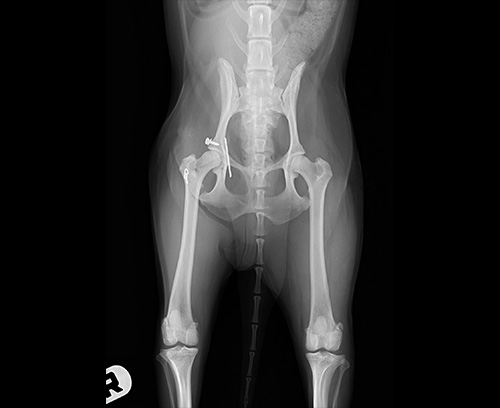

股関節脱臼(整復後)

股関節脱臼